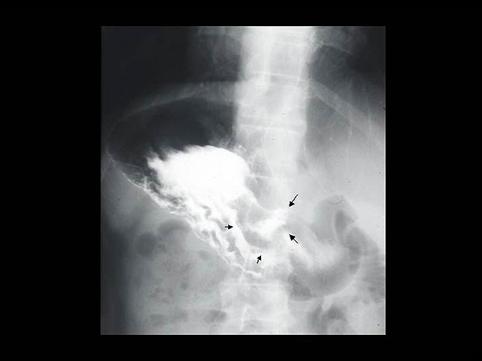

A case of gastric ulcer associated with a candida infection in a healthy adult.

Inflammatory or ulcerative disease / lesions/gastric ulcer

Stomach/Antrum

X-ray

25 - 29